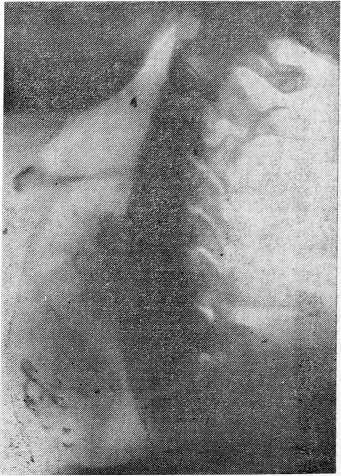

Помимо сужения трахеи отмечается неровность и зазубренность контуров. При прорастании опухоли в. просвет трахеи наряду с утолщением стенки трахеи в ее просвете определяется дополнительная тень опухоли (рис. 2 и 3).

Рис. 2. Больной К., 33 лет. Рентгено грамма шеи в прямой проекции.

Справа видна тень резко увеличенной щитовидной железы. Воздушный столб трахеи смещен влево, так что его левый контур выходит за край позвоночника.

Рис. 3. Рентгенограмма того же больного в правой боковой проекции.

Выявляется тень увеличенной щитовидной железы, в среднем отделе ее — единичные плотные вкрапления. Просвет трахеи на уровне С7 — Д1 конусовидно суживается за счет сдавления по передней и задней стенкам. Ретротрахеальное пространство на уровне С7 — Д1 расширено. Отмечается сближение подъязычной кости и хрящей гортани за счет давления снизу увеличенной опухолью щитовидной железы.